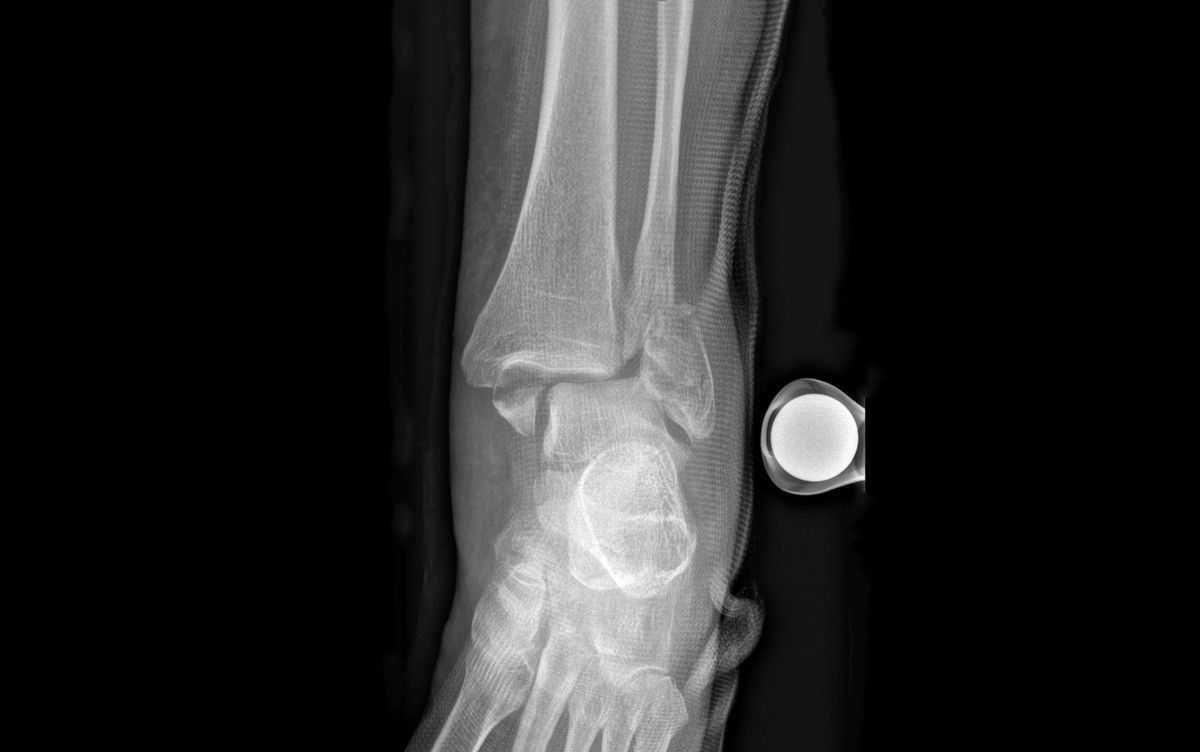

Die Schmerzen und die Schwellung über dem Aussen- und/oder Innenknöchel lassen bei der Untersuchung häufig auf eine Bandverletzung oder einen Bruch schliessen. Die definitive Diagnose wird jedoch erst anhand eines Röntgenbilds gestellt. Eine weiterführende Diagnostik mittels Magnetresonanztomographie (MRT bzw. engl. MRI für magnetic resonance imaging) bleibt unklaren Fällen mit hohem Verdacht auf zusätzliche Syndesmosenverletzung vorbehalten. Bei komplizierten Brüchen dient eine Computertomographie (CT) der besseren Erkennung oder dazu, knöcherne Zusatzverletzungen auszuschliessen.

Verschobene Brüche sollten operiert werden, um einer späteren Arthrose vorzubeugen *. Der richtige Zeitpunkt dafür hängt jedoch vom Zustand der Weichteile ab. Diese sollten nicht zu fest angeschwollen sein, da sonst die Haut nach der Operation nicht mehr richtig verschliesst. In Fällen mit starker Schwellung und instabilen Brüchen kann auch eine externe Fixation (Fixateur externe) notwendig sein *. Nach der Weichteilkonditionierung (abschwellende Massnahme) kann dann die definitive Frakturversorgung 5 bis 10 Tage später erfolgen.

Beim Eingriff werden die Knochenbruchstücke von Altblut gesäubert und wieder in ihre anatomische Form gebracht. Die Fixation erfolgt dann mittels Schrauben und/oder Platten. Sollte die Knöchelgabel aufgrund einer Syndesmosenverletzung instabil sein, ist womöglich eine temporäre Stellschraubenfixation erforderlich. Diese Stellschraube wird 8 Wochen später ambulant wieder entfernt. Die anderen Schrauben werden nur entnommen, falls sie stören – meistens nach einem Jahr oder etwas früher.